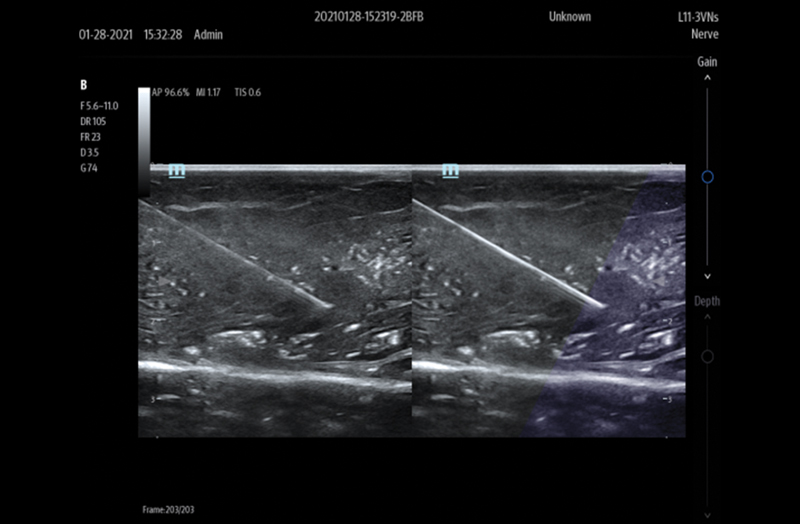

Needle Guidance